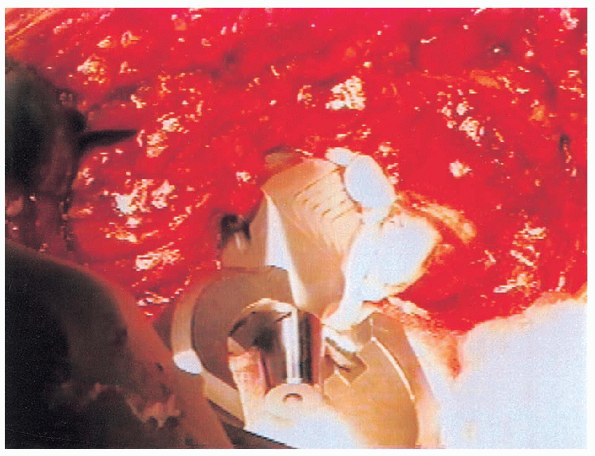

the acetabulum (Fig. 20-23). The acetabular component selected is next impacted into place in 40 degree of cup abduction and 10 degrees of anteversion (Figs. 20-24 and 20-25).

The component we use is approximately 0.75 mm larger in diameter than

labeled because of macro-texturing, resulting in increased interference

fit. Two screws placed into the posterior-superior quadrant (as

described by Wasielewski) are then used to augment initial stability

(rarely longer than 25 mm, because longer screws may exit the pelvis

and endanger surrounding neurovascular structures) (Figs. 20-26 and 20-27).